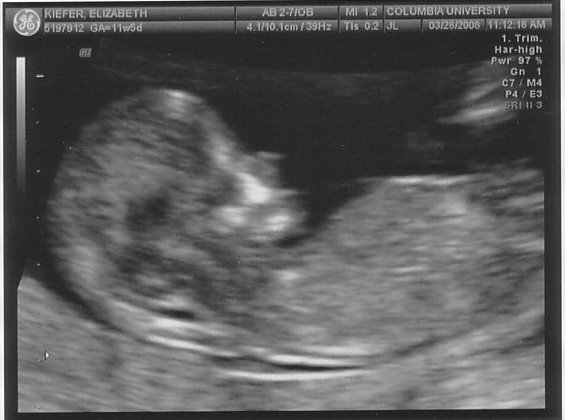

On Friday we headed uptown for our second ultrasound. Nobody told me that baby m0ves around in there at 12 weeks (thanks for the help, parenting books, keep up the good work!), so I just about freaked out when he arched his back and rubbed his face (or she/her, of course, we don’t find that out for another 6 weeks). Fortunately our tech was used to people gasping loudly. Sooooo cool.

In case you were wondering if I was going to be a stereotype of a dad, I’m including all 5 blurry blob pictures here. And if I had an hour long movie of same, I’d post that, too.